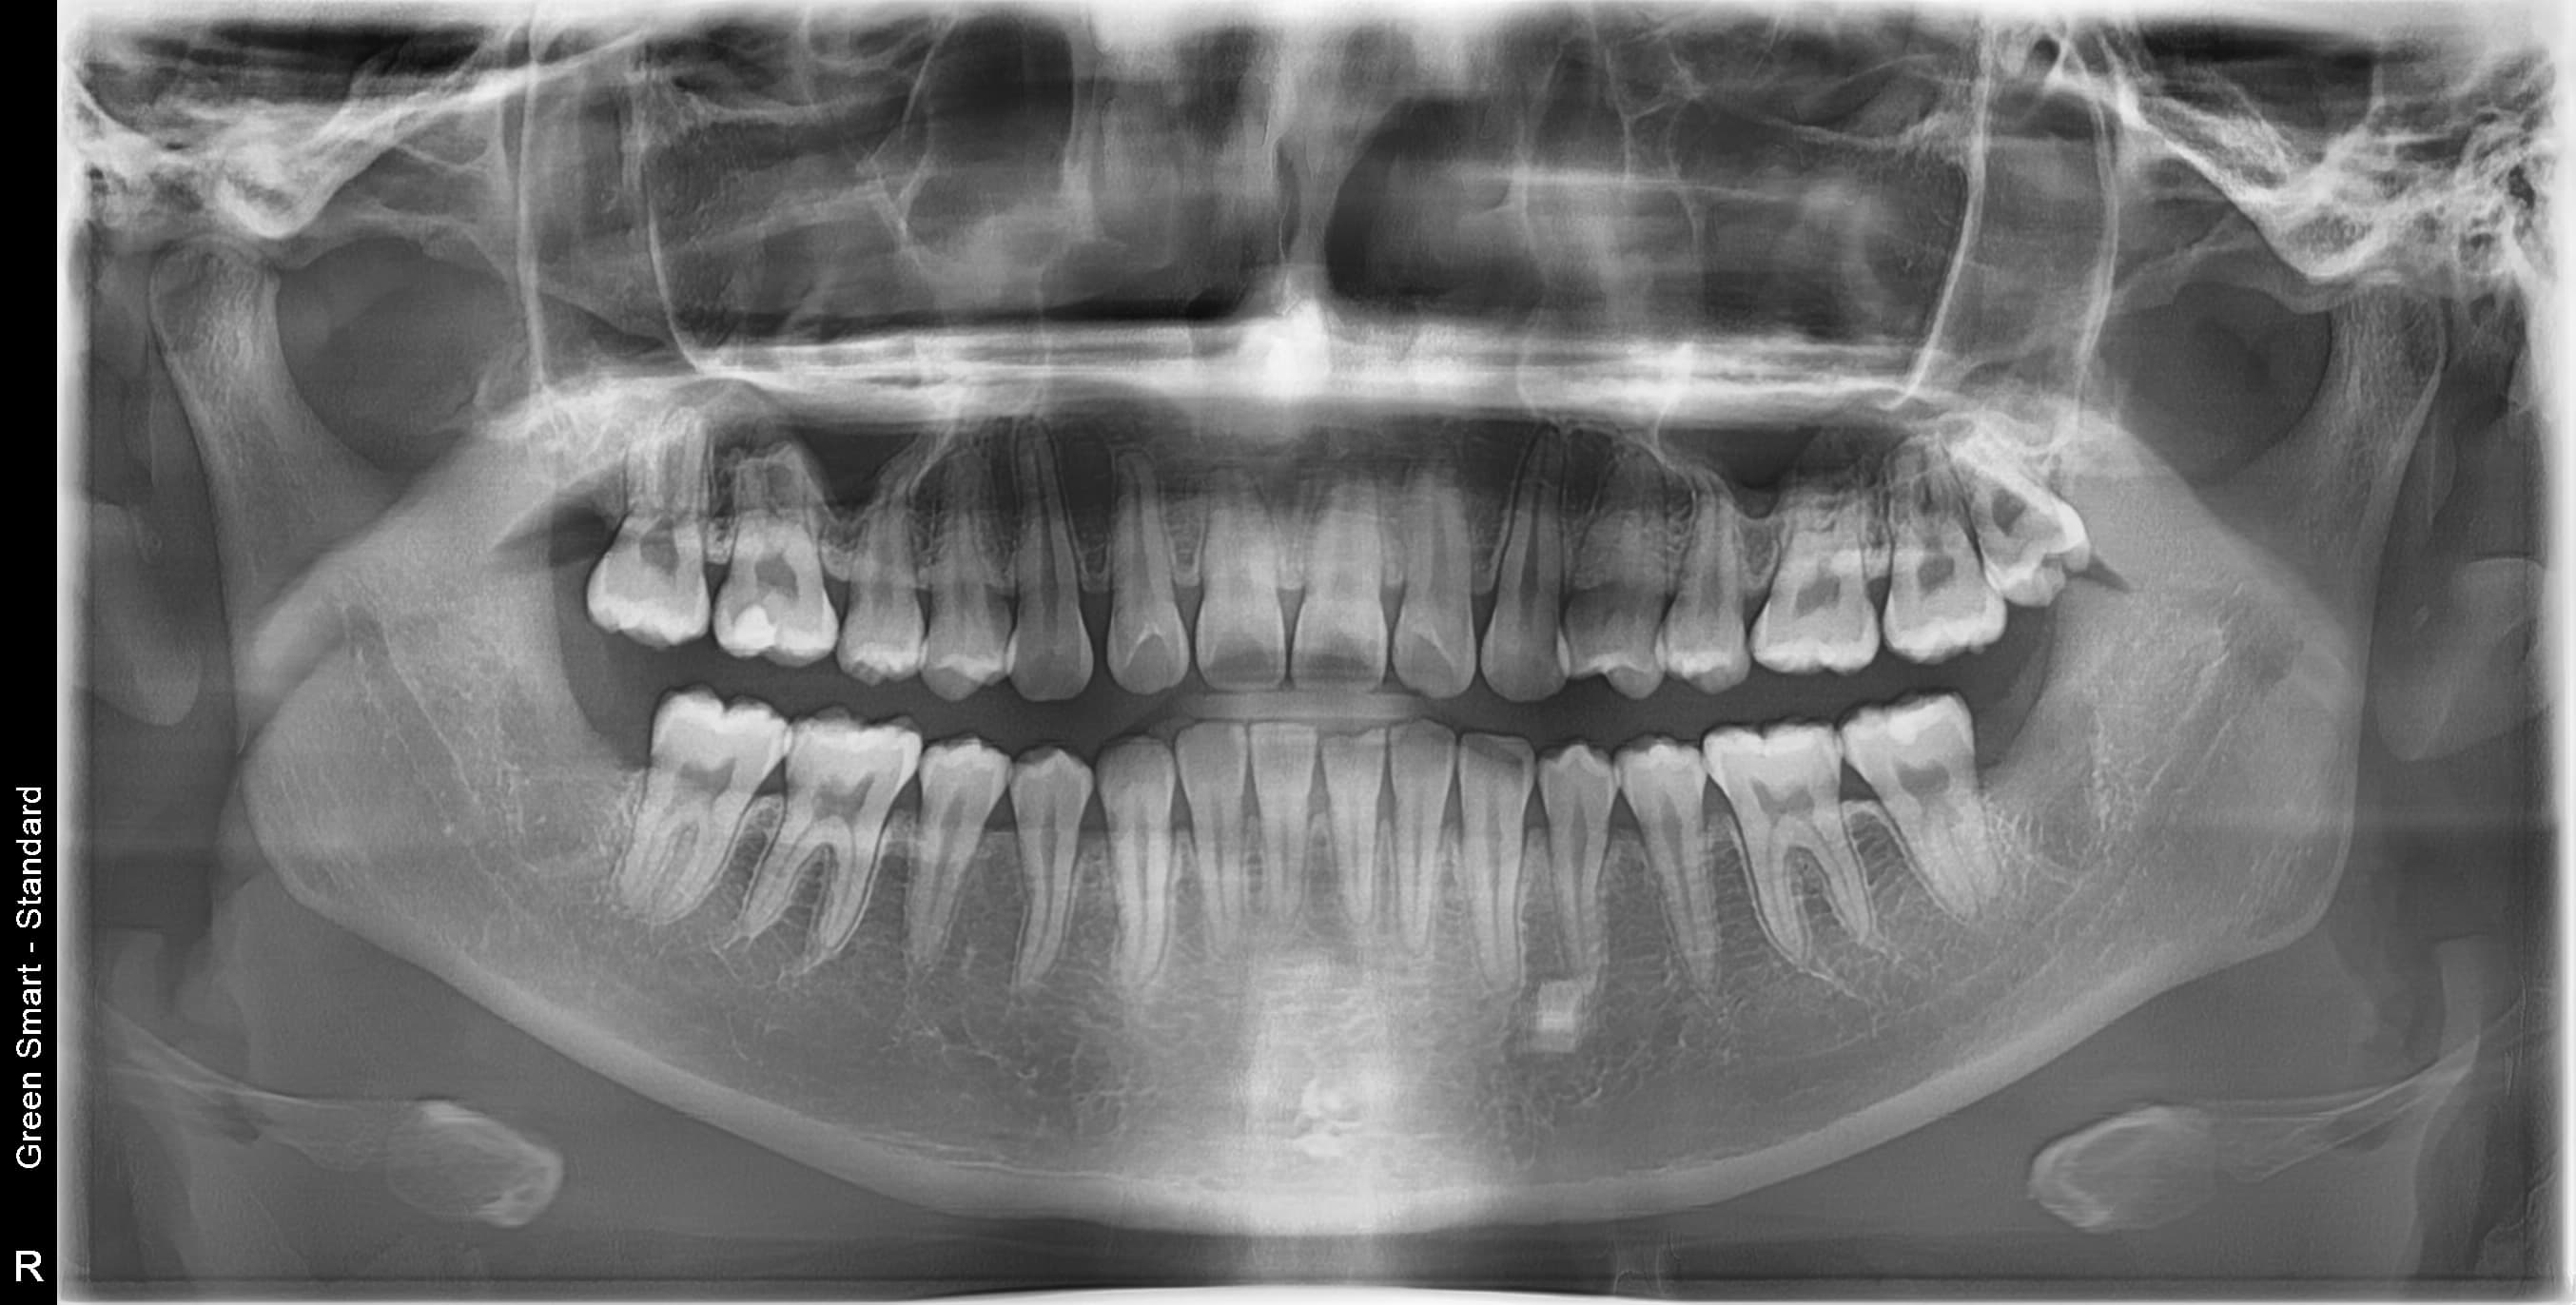

대학병원급 난이도 발치

일반 치과에서 "큰 병원 가보세요", "전문병원에서 빼세요" 이런 말 들어보셨나요?

복잡한 매복 사랑니 - 잇몸 속 깊이 묻혀있어도 OK

신경 근접 사랑니 - 신경 손상 걱정 없는 안전한 발치

수평 매복 사랑니 - 옆으로 누워있는 어려운 케이스도 가능

2,700건 이상의 발치 경험으로

대학병원 수준의 난이도도 안전하게 해결합니다

난이도 높은 사랑니도 뽑을 수 있나요?

네, 가능합니다. 경성 메디스 치과는 2,700건 이상의 발치 경험과 대학병원급 난이도 발치가 가능한 시스템을 갖추고 있습니다. 수평매복, 완전매복 등 일반 치과에서 큰 병원을 권유하는 어려운 케이스도 3D CT 정밀 진단으로 안전하게 발치합니다.